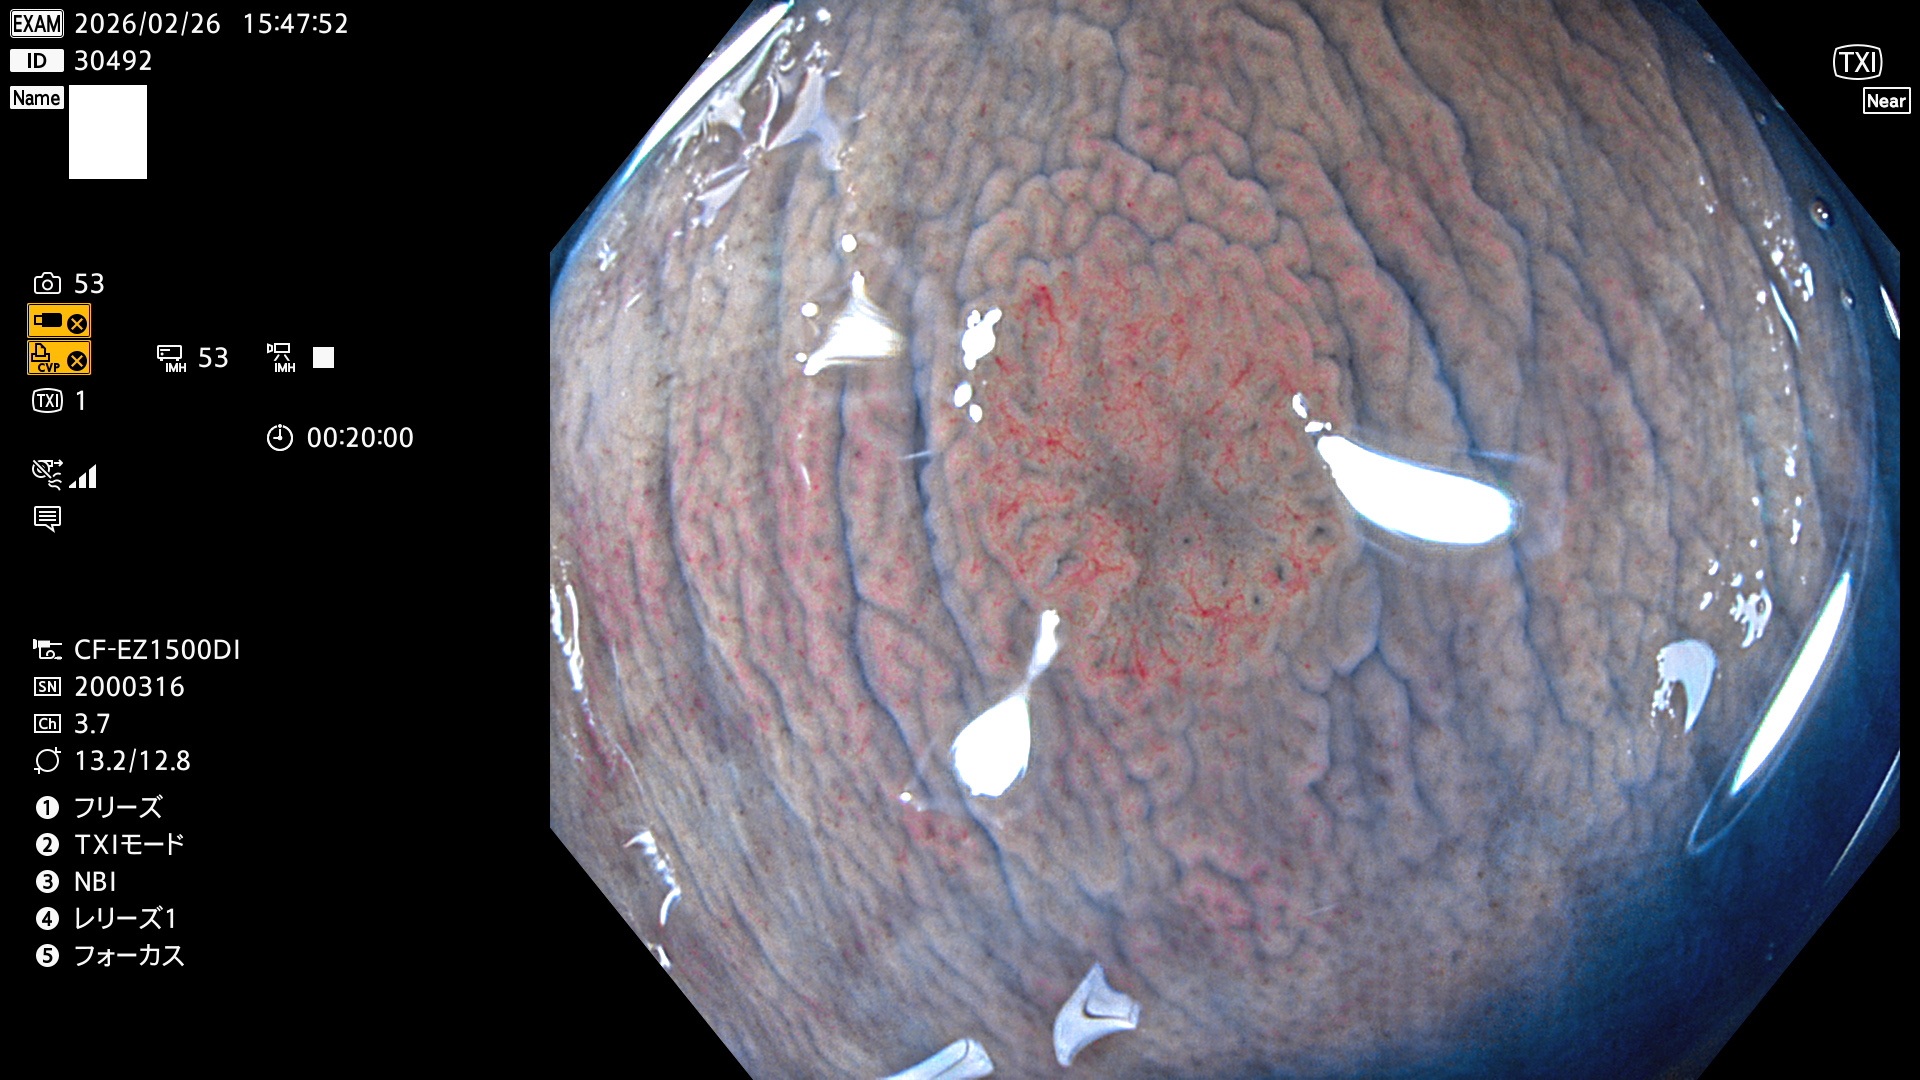

完全に平坦な物をUb、陥凹している物をUcと呼びます。Ubは認識が困難で、Ucはびらん(炎症)と紛らわしいために見落とされやすく、「内視鏡後・大腸癌」の原因になります。

専門的)Uc=De Novo癌? 内視鏡の解像度が低かった時代、このような説もありました。しかし今日の高精度内視鏡では良性の微小なUc型腺腫(APC遺伝子異常の腺腫)が日常的に見つかります。Ucこそが多段階発癌(Adenoma-Carcinoma Sequence)のMain Routeです。

毎週の検査(木・金・土・日)に発見されたUbとUc型・腺腫を、その週の日曜の夜にUPし1週間、提示します。

2026年2月26日〜3月1日の4日間(40件)2個 (Uc_ADR=2個/40人=5%)